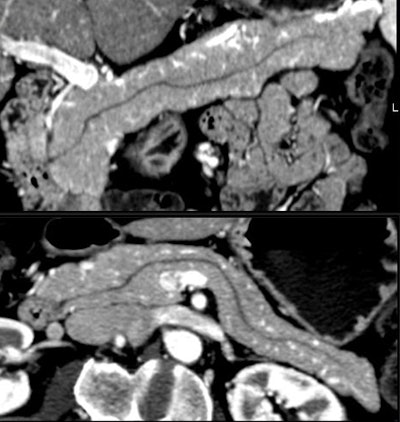

Small cystic lesions not worrisome for malignancy under 3 cm include side branch IPMNs, and serous microcystic adenomas, which are easily characterized by their honeycomb matrix that is also easily seen on ultrasound, Jeffrey said.

Serous cystic tumors are by far the most common pancreatic cystic lesions, Jeffrey said. They are nearly always microcystic, with macrocystic serous lesions occurring in about 4% of cases. They also are benign and can be managed with follow-up but not surgery, he said.

In Jeffrey's Stanford radiology group, Kilpatrick et al recently followed 156 patients with cysts smaller than 3 cm and no worrisome features at CT over three years. In all, 86 had follow-up of more than two years (n=28), one to two years (n=13), six to 12 months (n=22), and less than six months (n=23).

Nineteen of the 156 patients had surgery, while only three cases were malignant, Jeffrey said. Most important, all malignancies had solid tissue within the lesion at CT. Interval growth was also a predictor. Lesions grew in seven cases, including two of the three malignancies, Jeffrey said of the study (Abdominal Imaging, January-February 2007, Vol. 32:1, pp. 119-125).

"The take-home message here is that those that have solid internal tissue or enlarge over time have potential for malignancy," he said. "Interval growth was seen in seven cases, two of which were malignant, so obviously benign lesions can also grow over time."